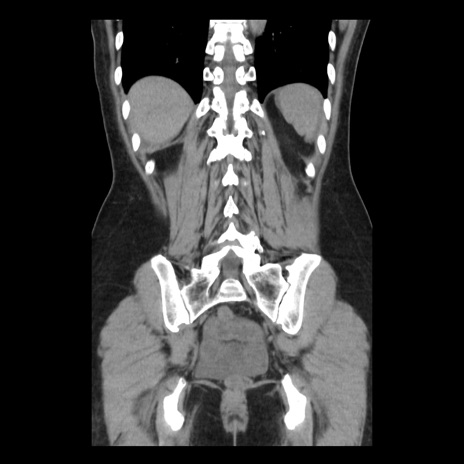

症例10(冠状断像)

【症例】 50歳代女性

【主訴】 腹痛

【現病歴】前日生レバーを食べた。今朝に排便あり。 昼前に突然発症の腹痛を生じ、当院救急外来を受診した。

【既往歴】 子宮筋腫にてで子宮全摘後

【身体所見】 意識清明、腹部:平坦、軟、下腹部やや左を中心に圧痛・反跳痛あり、筋性防御あり

【データ】WBC 7800、CRP 0.07